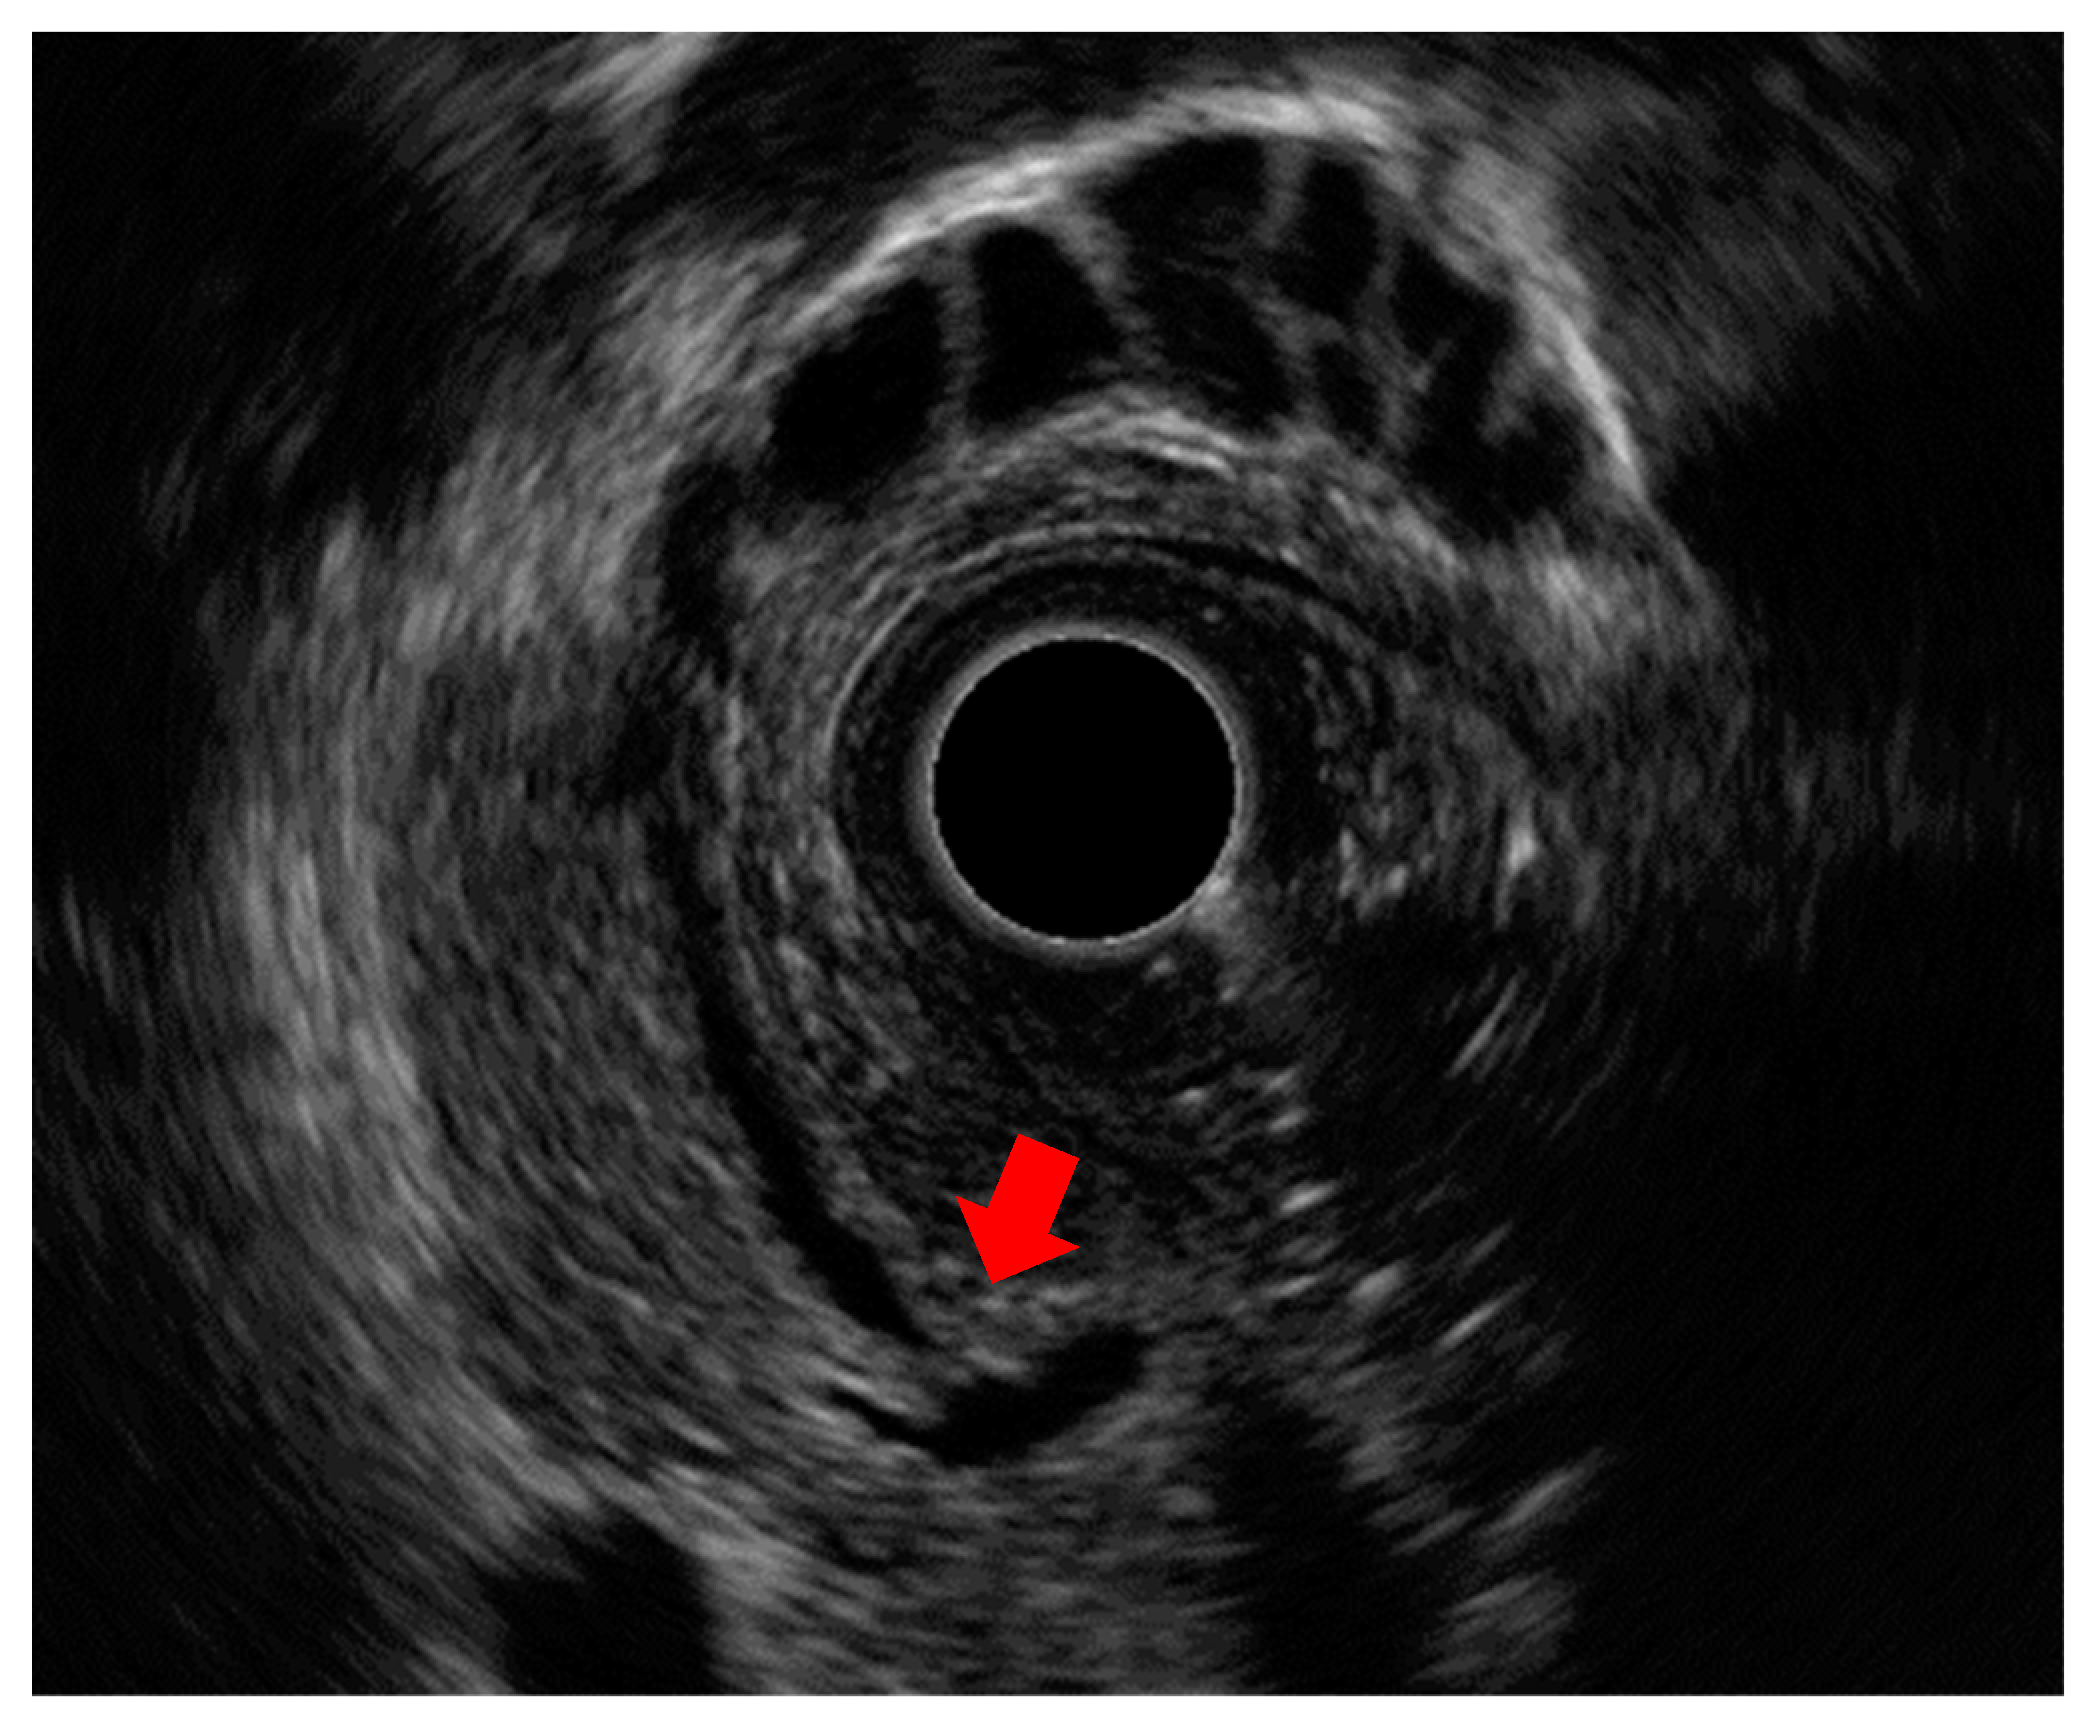

- Alper, E.; Arabul, M.; Buyrac, Z.; Baydar, B.; Ustundag, Y.; Celik, M.; Ünsal, B. The use of radial endosonography findings in the prediction of cholangiocarcinoma in cases with distal bile duct obstructions. Hepatogastroenterology 2013, 60, 678–683. [Google Scholar] [CrossRef] [PubMed]

- Meister, T.; Heinzow, H.S.; Woestmeyer, C.; Lenz, P.; Menzel, J.; Kucharzik, T.; Domschke, W.; Domagk, D. Intraductal ultrasound substantiates diagnostics of bile duct strictures of uncertain etiology. World J. Gastroenterol. 2013, 19, 874–881. [Google Scholar] [CrossRef] [PubMed]